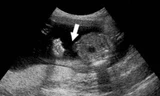

Hình ảnh khối thai đá trong cơ thể bà Sáu

Qua thăm khám và chụp X quang, các bác sĩ phát hiện vùng tiểu khung có khung xương thai nhi (gồm hộp sọ, cột sống, các xương sườn và xương đùi) và chẩn đoán: có thai hết lưu trong ổ bụng.

Qua chụp chiếu, các BS xác định khối u có chiều dài khoảng 15-20cm, chưa rõ cân nặng là bao nhiêu. “Khi sờ nắn, thăm khám thì bà thấy đau tại khu vực có khối u này, còn để bình thường thì không” – BS Quang cho biết thêm.

Khối u cũng chưa xác định được nằm trong hay ngoài tử cung hay tuổi thai là bao nhiêu.